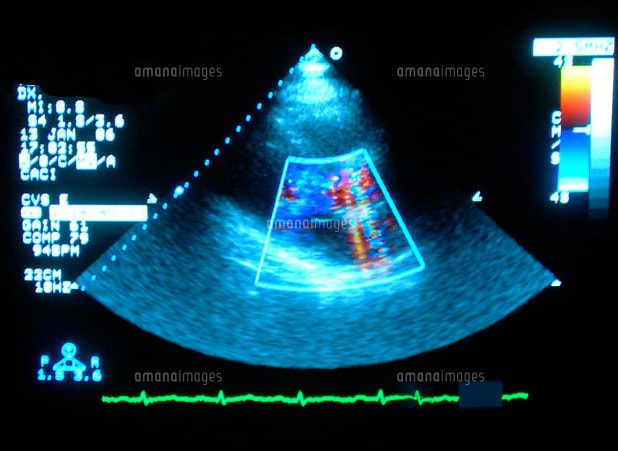

心臓超音波検査

心臓超音波検査(心エコー)とは、人の耳には聞こえないほどの高周波数の超音波を心臓に発信して、返ってくるエコー(反射波)を受診し、心臓の様子を画像に映し出して診断する検査です。

超音波は、臓器や組織にあたると、歪が生じるので、心臓からエコーを受信して画像に映し出し、心臓の動きを観察します。X線撮影やRI検査のように放射線による被曝の心配がありませんので、妊婦や乳幼児でも安心して受けることができます。

この検査を行なう目的は二つあり、一つは心臓の形の異常を発見する形態的診断、もう一つは心臓の働きを見る機能的診断です。